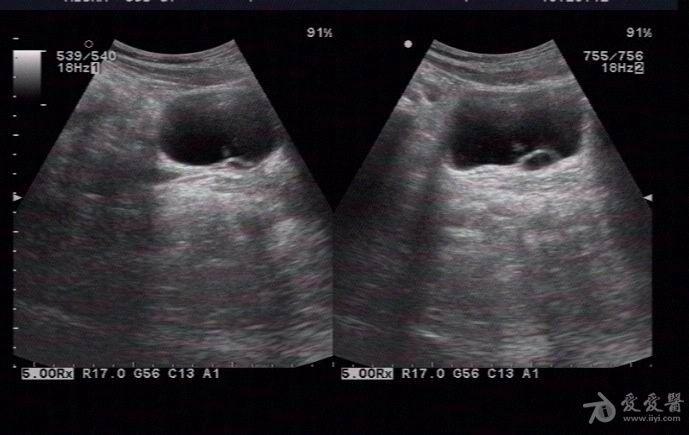

输尿管囊肿 - 超声医学讨论版 - 爱爱医医学论坛

超声故事:儿童输尿管囊肿_扩张

输尿管末端囊性扩张 - 超声医学讨论版 - 爱爱医医学

腹部超声:膀胱输尿管反流_扩张